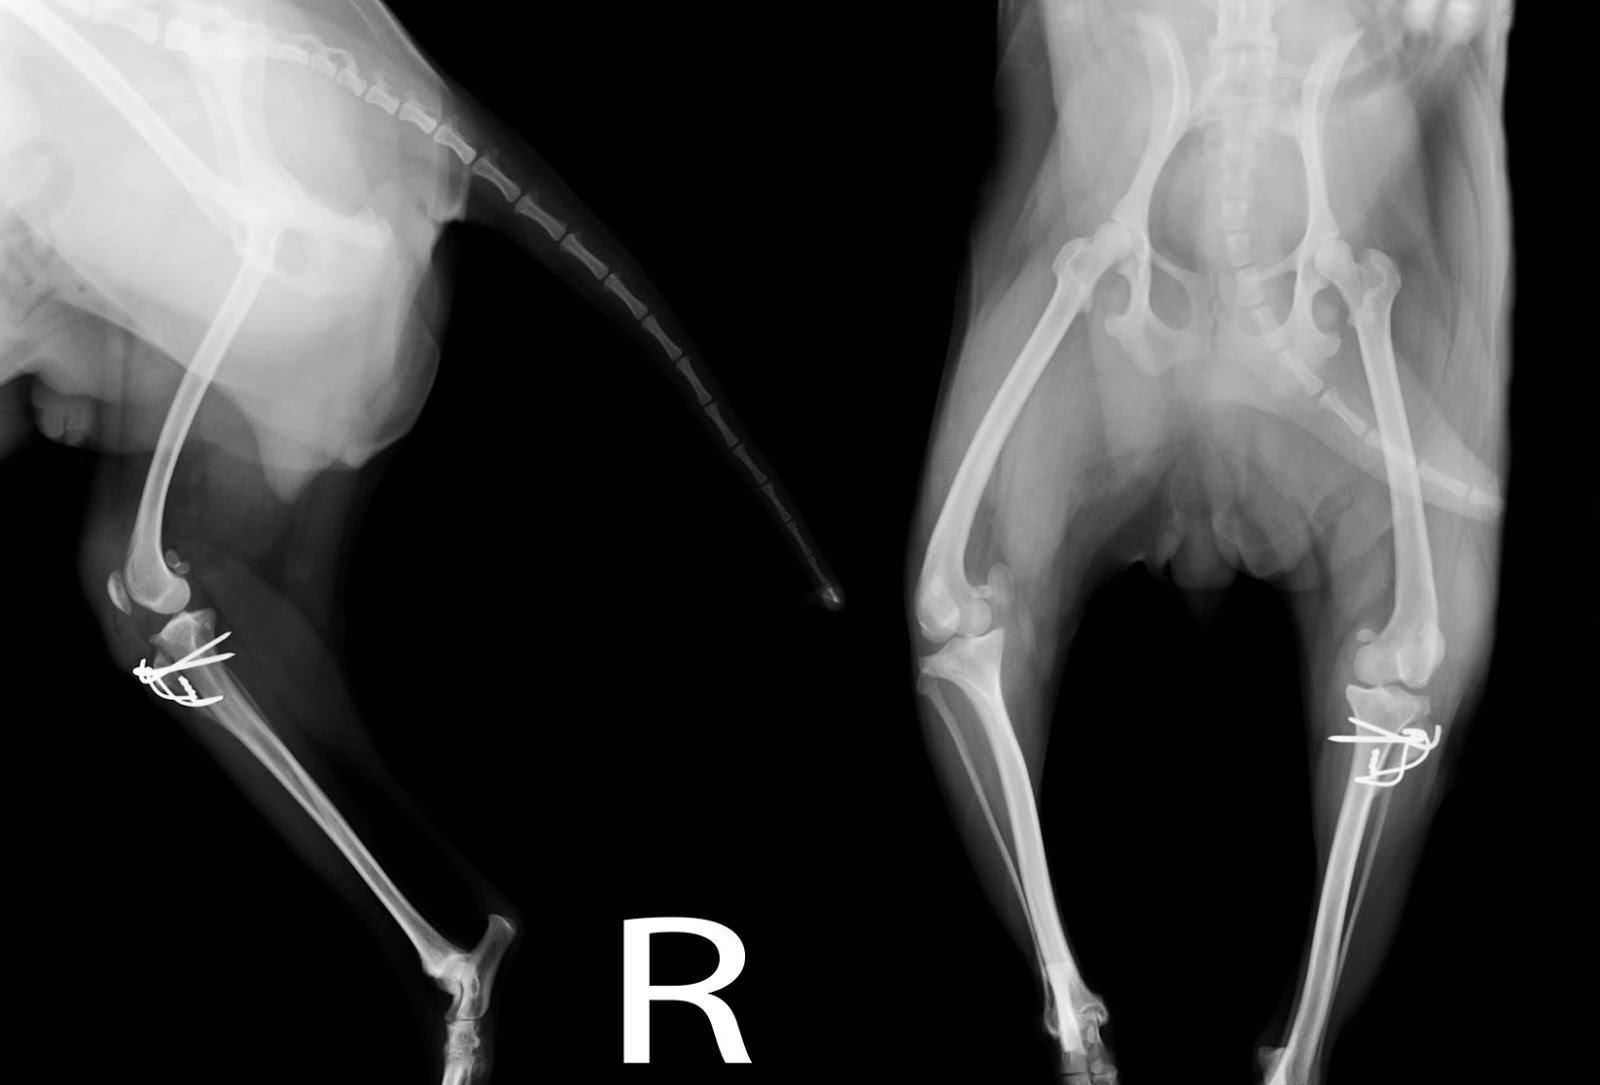

WebGrado I. Luxación de rótula intermitente, causando cojera de la extremidad solo cuando está fuera de su sitio. Son perros que cada tres o cuatro pasos levantan la. WebPara confirmar la sospecha de luxación patelar en perros, el veterinario palpará la rodilla cuidadosamente. Además, comprobará en qué medida y en qué dirección se luxa la. WebUna luxación rotuliana en perros es una de las anomalías más frecuentes de la articulación de la rodilla en los perros. La condición es más común en razas de perros de juguete y. WebEjercicios Para Luxación De Rótula En Perros Hola y gracias por visitar nuestro blog. En este artículo hablaremos de un producto de mucha calidad y muy buscado en tiendas en. WebClasificación de la luxación de rótula en perro. Existen varios sistemas de clasificación de la severidad de la luxación, pero el más usado por los clínicos es el de Roush, que.

WebUna luxación rotuliana en perros es una de las anomalías más frecuentes de la articulación de la rodilla en los perros. La condición es más común en razas de perros de juguete y. WebEjercicios Para Luxación De Rótula En Perros Hola y gracias por visitar nuestro blog. En este artículo hablaremos de un producto de mucha calidad y muy buscado en tiendas en. WebClasificación de la luxación de rótula en perro. Existen varios sistemas de clasificación de la severidad de la luxación, pero el más usado por los clínicos es el de Roush, que. WebA continuación apretaremos la pelota con ambas rodillas, intentando que las dos piernas hagan la misma fuerza. Elevar pierna inferior: nos colocaremos. WebShow more. 🦴LUXACIÓN DE RÓTULA EN PERROS Hoy os hablamos de la LUXACIÓN DE RÓTULA en perros y os contamos el caso de Lupe, esta YorkShire que padecía un. WebLa operación de luxación de rotula para perros significa conseguir que el hueso no duela al perro y pueda caminar y correr sin problemas. Se trata de la reconstrucción del hueso y. WebEn la situacion de las rodillas, existen varios ejercicios que se tienen la posibilidad de llevar a cabo, pero los más destacados son: Los paseos acuáticos asisten a recobrar la. WebLa otra rotula nunca le ha quedado al 100% y sigue casi igual de coja que antes d la operacion. Esta perra tuvo cachorros (yo no sabia que eso se heredaba) y uno de ellos. WebMasoterapia para perros con luxación de rótula. La terapia de masaje y el ejercicio correctivo pueden beneficiar a los perros con luxación leve de rótula. El.